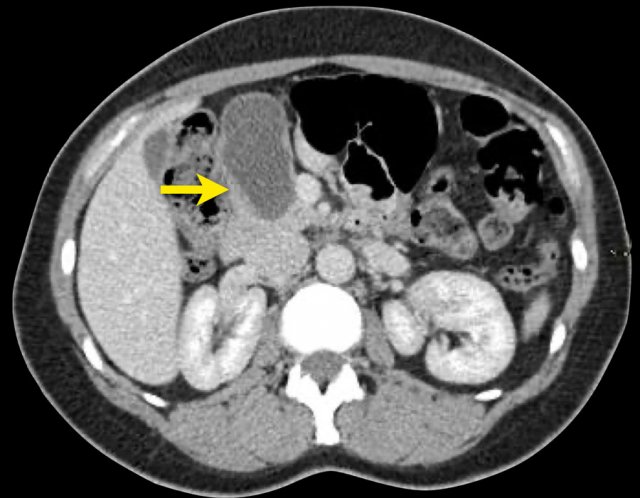

CT-images of an IPMN with a dilated pancreatic duct (blue arrows).

Notice enhancing solid nodule in the pancreatic head (red arrow).

Continue with the ultrasound-image.

The US-image shows a large branch-duct component within the pancreatic head.